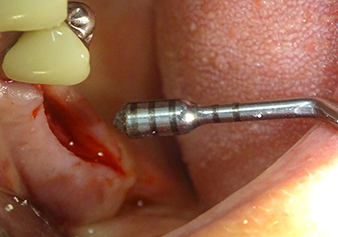

A 49-year-old female patient, a non-smoker and with nothing remarkable in her general medical history, was referred to our oral surgery practice for surgical extraction of tooth 16 and subsequent implantation. After the extraction, the patient experienced mild sinusitis trouble with the resultthat we initially waited six months before carrying out the measure. The residual bone height at the planned implant position measured 3-4 mm (Fig. 1 and 2).

Preoperative findings: The alveolar ridge has healed well, including sufficiently broad, keratinised gingiva

Fig.1: Preoperative findings: The alveolar ridge has healed well, including sufficiently broad, keratinised gingiva.

Following atraumatic preparation of the mucoperiosteal flap, the implant position was marked with the I1 instrument and the site prepared – until initial resistance was felt. Piezosurgical instruments were used in an up and down movement without any pressure being exerted. The piezoelectric vibration produced the desired and efficient cavitation.

The I2A instrument (diameter 2.0 mm) was then used to perforate the sinus floor intermittently and on the smallest scale possible. This special piezosurgical method ensures that the Schneiderian membrane is not damaged. When the Z25P was used, the membrane was already lifted slightly by the coolant supplied via the instrument tip (Fig. 3). The coolant quantity was just 50% in order to avoid high pressure in the implant bed.

The Schneiderian membrane is carefully detached with the Z25P instrument (phase 1)

Fig.3: Following marking of the implant position and initial expansion of the bed, the Schneiderian membrane is carefully detached with the Z25P instrument (phase 1).